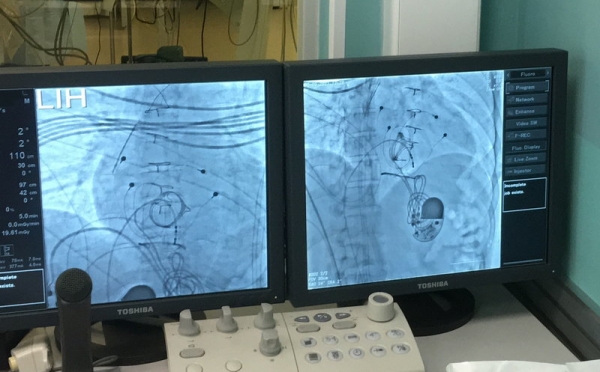

В клинику в плановом порядке поступил 43-летний мужчина. Ранее установленный электрокардиостимулятор (ЭКС) перестал выполнять свою функцию и требовал срочной замены. Установить ЭКС стандартным методом под ключицу было невозможно, поэтому пришлось зафиксировать его в животе пациента.

15 лет назад мужчине установили электрокардиостимулятор в стандартном месте в подключичной области. Спустя некоторое время у него развилось опасное осложнение – инфекционный эндокардит – воспаление в сердце. Поэтому в 2013 году ему провели сложную открытую операцию. Удалили ранее установленный аппарат и одновременно заменили клапан сердца на биопротез. Именно тогда электрокардиостимулятор был установлен в передней брюшной стенке.

– Извлечь аппарат было технически сложно, но мы справились, удалили старый аппарат и установили новый в прямую мышцу живота с фиксацией к мышце, – отметил проводивший операцию заведующий кардиологическим отделением, рентгенохирург Михаил Емельяненко – Послеоперационный период прошел успешно, самочувствие пациента значительно улучшилось, и он был выписан домой.